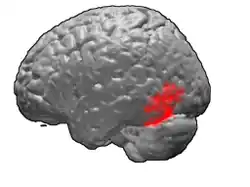

Brodmann area 37, or BA37, is part of the temporal cortex in the human brain. It contains the fusiform gyrus which in turn contains the fusiform face area, an area important for the recognition of faces.

This area is also known as occipitotemporal area 37 (H). It is a subdivision of the cytoarchitecturally defined temporal region of cerebral cortex. It is located primarily in the caudal portions of the fusiform gyrus and inferior temporal gyrus on the mediobasal and lateral surfaces at the caudal extreme of the temporal lobe. Cytoarchitecturally, it is bounded caudally by the peristriate Brodmann area 19, rostrally by the inferior temporal area 20 and middle temporal area 21, and dorsally on the lateral aspect of the hemisphere by the angular area 39 (H) (Brodmann-1909).[1]